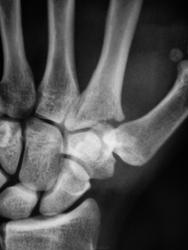

Пол пациента: Мужской пол Тип патологии: Травма Область исследования: Скелетно-мышечная система Методы исследования: Rg Травма. Пациент направлен на рентгенографию лучезапястного сустава. https://radiomed.ru/sites/default/files/styles/case_slider_image/public/user/12/2.pb240009.jpg?itok=Q_2dED98 https://radiomed.ru/sites/default/files/styles/case_slider_image/public/user/12/3.pb240009a.jpg?itok=_USHqTOg https://radiomed.ru/sites/default/files/styles/case_slider_image/public/user/12/4.pb240010a.jpg?itok=euelnlI2 ID:17025 Чт, 24/11/2011 - 19:49 #1 tatyana Не на сайте Был на сайте: 4 года 1 месяц назад Зарегистрирован: 24.06.2009 - 08:33 Публикации: 2090 перелом основания 2 пястной кости "самоуверенность дилетантов - предмет зависти профессионалов" Чт, 24/11/2011 - 21:18 #2 nnemo Не на сайте Был на сайте: 11 лет 1 месяц назад Зарегистрирован: 13.09.2011 - 18:32 Публикации: 561 tatyana wrote: перелом основания 2 пястной кости +1 Чт, 24/11/2011 - 22:14 #3 И.Бондаренко Не на сайте Был на сайте: 19 часов 41 минут назад Зарегистрирован: 13.09.2011 - 22:55 Публикации: 9206 Оскольчатый перелом основания 2 пястной кости, со смещением. Чт, 24/11/2011 - 22:26 #4 Bob Не на сайте Был на сайте: 11 лет 11 месяцев назад Зарегистрирован: 20.08.2011 - 20:06 Публикации: 218 +1 Пт, 25/11/2011 - 02:28 #5 Makcimalist Не на сайте Был на сайте: 11 лет 9 месяцев назад Зарегистрирован: 08.05.2010 - 14:28 Публикации: 1994 И.Бондаренко wrote: Оскольчатый перелом основания 2 пястной кости, со смещением. И я вскладчину! -------------- "Просто, по видимости, не видеть логики в очевидных вещах - это тоже одно из свойств некоторых умов, наряду с грустными думами о свойствах ума других." © Vega 08/10/2011

перелом основания 2 пястной кости

Оскольчатый перелом основания 2 пястной кости, со смещением.